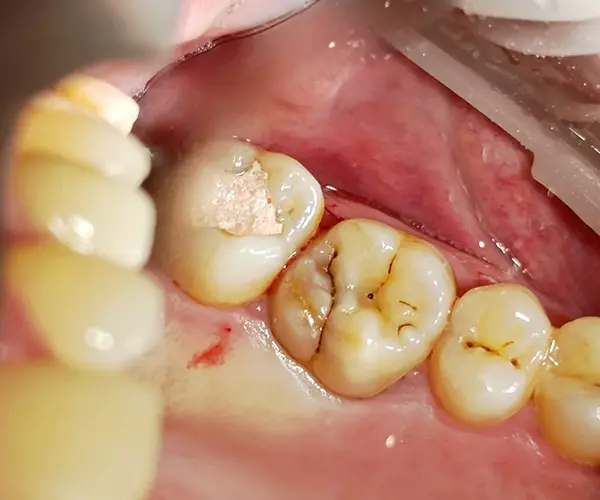

По результатам КЛКТ у пациента был выявлен дефект твердых тканей на дистальной поверхности зуба 2.6. Основной вызов — восстановить анатомию зуба, сохранив плотный апроксимальный контакт и обеспечив идеальную адаптацию композита к тканям зуба.